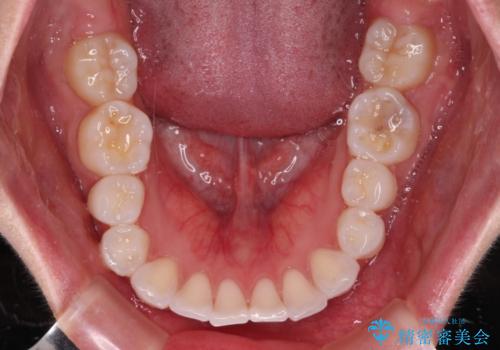

- 八重歯と、それによる正中のズレを気にして来院された患者様です。

口元の突出感は気にしていなかったため、上顎の左右第一小臼歯を抜歯することで、八重歯の解消と上顎の正中を改善していくこととしました。

奥歯の咬み合わせを維持しながら正中位置を改善するために、補助装置を使用しました。

予定より期間がかかりましたが、上下の正中位置を綺麗に一致させることができました。